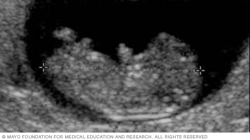

Below is an image of the base of the brain, called the cerebellum. This type of image usually is taken during an ultrasound done between 18 and 22 weeks of pregnancy.

The cerebellum is the part of the brain that controls muscle coordination and balance. Checking its shape on an ultrasound can help the health care team find neural tube defects. The neural tube forms in the first few weeks of pregnancy. The top of the tube becomes the brain. The rest of it becomes the spinal cord. Problems in neural tube development may lead to conditions such as spina bifida, in which part of the neural tube doesn't develop or close correctly. This can lead to problems in the spinal cord and in the bones of the spine.